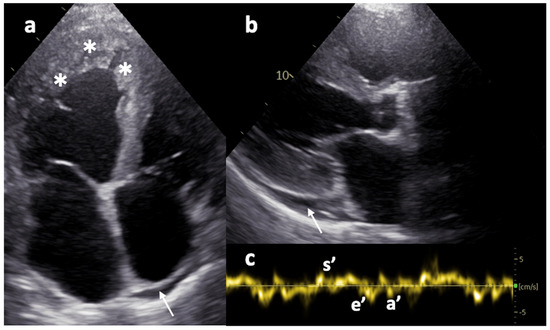

Digenic Contribution of Heterozygous ALPK3 and TRIM63 Variants to End-Stage Hypertrophic Cardiomyopathy in a Young Adult

by Olga S. Chumakova, Natalia V. Milovanova, Elena A. Mershina, Sergey I. Kutsev and Ekaterina Y. Zakharova

Cardiogenetics 2026, 16(1), 1; https://doi.org/10.3390/cardiogenetics16010001 - 1 Jan 2026

Hypertrophic cardiomyopathy (HCM), the most common inherited cardiac disorder, is usually caused by pathogenic variants in sarcomeric genes and is inherited in an autosomal dominant manner. Around 5% of cases are caused by variants in non-sarcomeric genes, which may involve alternative modes of [...] Read more.

Hypertrophic cardiomyopathy (HCM), the most common inherited cardiac disorder, is usually caused by pathogenic variants in sarcomeric genes and is inherited in an autosomal dominant manner. Around 5% of cases are caused by variants in non-sarcomeric genes, which may involve alternative modes of inheritance. This study presents the first reported case of HCM associated with digenic contribution of heterozygous variants in two non-sarcomeric genes: ALPK3 and TRIM63. The patient was incidentally diagnosed with non-obstructive HCM in childhood and developed extreme myocardial hypertrophy with moderate heart failure at the age of 18. Rapid progressive left ventricular dysfunction promptly resulted in death at the age of 26. Genetic testing with an extended HCM panel identified no sarcomeric variants but revealed two truncating variants in the ALPK3 and TRIM63 genes. Whole-genome sequencing excluded any other causes of the disease. Heterozygous ALPK3 variants are typically associated with late-onset HCM, whereas TRIM63 variants are only considered pathogenic in a recessive state. This case, therefore, suggests a synergistic contribution of both variants to the development of a severe phenotype. The potential mechanisms of interaction between the protein products of ALPK3 and TRIM63 within the M-band of the sarcomere are discussed. Full article

Show Figures

Figure 1